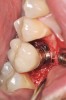

Fig 10. Fractured zirconia abutment with a titanium base.

Figure 10

Fig 11. Fractured all-zirconia abutment.

Figure 11

The increase in demand for esthetically pleasing implant restorations has led clinicians to embrace the use of all-ceramic abutments. This has subsequently increased abutment fractures (Figure 10 and Figure 11)22,23 and decementation of the ceramic crown and corresponding abutment.24 Use of zirconia abutments is relatively new in implant dentistry and has limited long-term follow-up data. Time will tell whether this technology is successful.